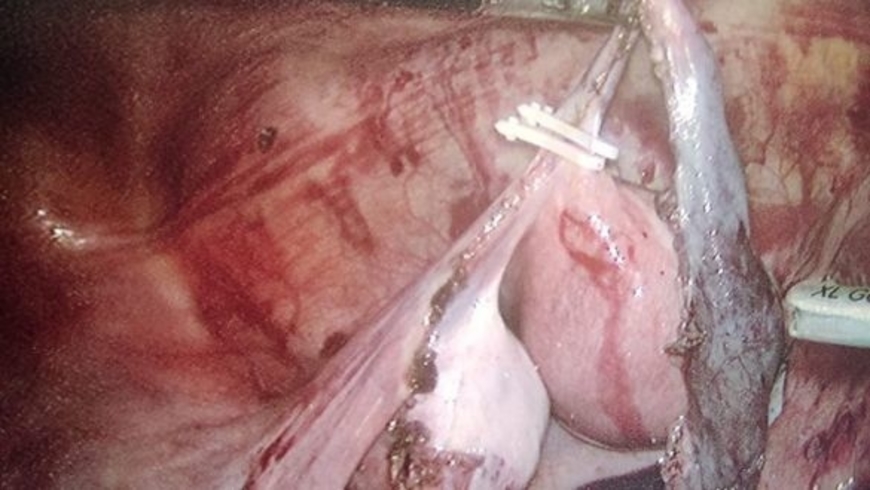

تمكن فريق طبي وتمريضي، يتكون من مختصين في طب النساء والتوليد، والإنعاش والتخذير، والجراحة العامة وجراحة المسالك البولية، بالمستشفى الإقليمي الأطلس الكبير بأزيلال، مساء أمس من اجراء عملية جراحية دقيقة، تعد الأولى من نوعها على صعيد الجهة، لسيدة في عقدها الثاني كانت تعاني من حمل خارج الرحم(GEU).

ونُقلت السيدة الحامل إلى المستشفى وهي في حالة حرجة، ليتم إخضاعها لفحوصات دقيقة، باشر بعدها الطاقم الطبي إجراء عملية جراحية لها بواسطة المنظار، وهي العملية التي مرت في ظروف جيدة، مكنت السيدة المستفيدة من تجنب المضاعفات والآثار المترتبة عن هذا الحمل.

بلاغ صادر عن المديرية الجهوية للصحة بجهة بني ملال-خنيفرة، أكد أن “نجاح هذه العملية الجراحية الدقيقة، تم بفضل خبرة وتجربة الفريق الطبي والتمريضي الذي أشرف على العملية من جهة، وإلى المعدات والتجهيزات الطبية المتقدمة التي أضحى يتوفر عليها المستشفى الإقليمي بأزيلال، والتي تندرج في إطار تنزيل استراتيجية وزارة الصحة الهادفة إلى تقليص وفيات الأمهات والمواليد الجدد والأطفال خصوصا في العالم القروي”.